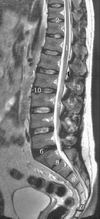

脊椎斷層在骨、關節和肌的成像方面,B超圖像的分辨力不如CT和MRI,但它具有實時和任意角度掃描等優點,適宜手術和運動狀態中套用。CT利用橫斷層和多角度掃描、矢、冠狀斷層影像重建、三維圖像及脊髓造影等技術可充分展示脊柱區的複雜結構,但其優勢在骨及關節成像。MRI可直接獲取橫、矢、冠、斜狀斷層圖像,軟組織對比優良,無需脊髓造影便可清晰顯示脊髓結構,還可觀察脊髓和髓核的生化變化,故一般認為MRI是檢查脊髓和髓核的首選影像方法。脊柱區的斷層解剖研究多採用斷層標本與MRI或CT相對照,抑或直接套用影像技術的方法進行,單純的標本研究很少。在椎靜脈系、關節突關節的年齡變化、脊柱和脊髓的發育、椎間盤的面積、體積、厚度及其與年齡的關係等的斷層影像解剖學研究方面還需深入開展。